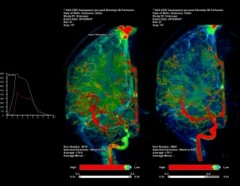

脳血管内治療におけるイメージガイダンスで 必要とされる情報を効率よく術者に提供するために、「NeuroSuite」では様々なアイテムをライナップしている。改良された新型頭部固定具*1、MR/CT画像とのオーバーレイによる3Dロードマッピング機能*1、脳血流の潅流状態を評価する2D Perfusion*1、そしてこれらを術中にモニタリングする大型マルチレイアウトモニタ FlexVisionXL*1により脳血管内治療をより安全により確実にサポートする。

アーチファクトを低減し理想的なサポートを実現

比較評価可能

リアルタイムに表示可能